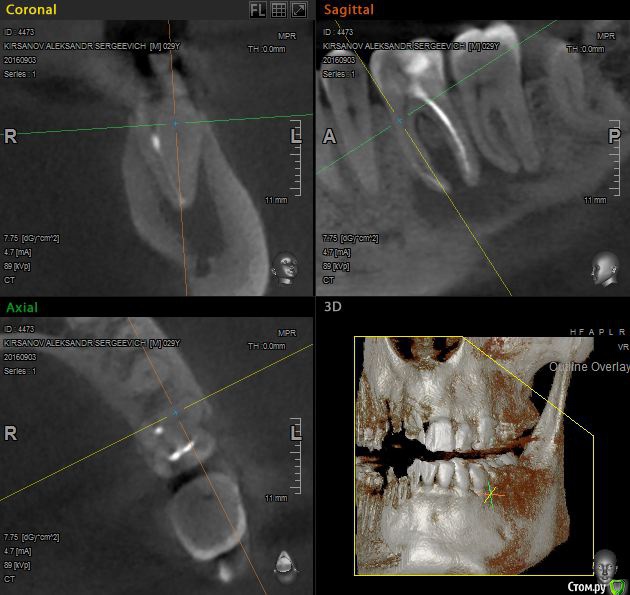

St. Опубликовано 12 ноября, 2016 Поделиться Опубликовано 12 ноября, 2016 Выложу скрины приложенного КТ. Так ответов будет больше. Есть пропущенный канал в 6 зубе. И нужно проверить на жизнеспособность соседний 7. Я бы рекомендовала попробвать перелечить и понаблюдать. Но Вы должны для себя понимать что перелечивание каналов очень сложная, дорогая и непрогнозируемая процедура. Хотя вероятность успеха достаточно высока. Если хотите гарантий - тогда удаление и имплант как восстановится кость. Еще хорошо бы знать как давно лечили каналы в этом зубе, как он вел себя после лечения, беспокоит ли сейчас? 2 Ссылка на комментарий

St. Опубликовано 12 ноября, 2016 Поделиться Опубликовано 12 ноября, 2016 11, 21 по кт без особенностей. Так что артефакты скорее всего. В 23( левый клык) есть тоже воспаление на корне. Нужно планово перелечиавать. Ссылка на комментарий